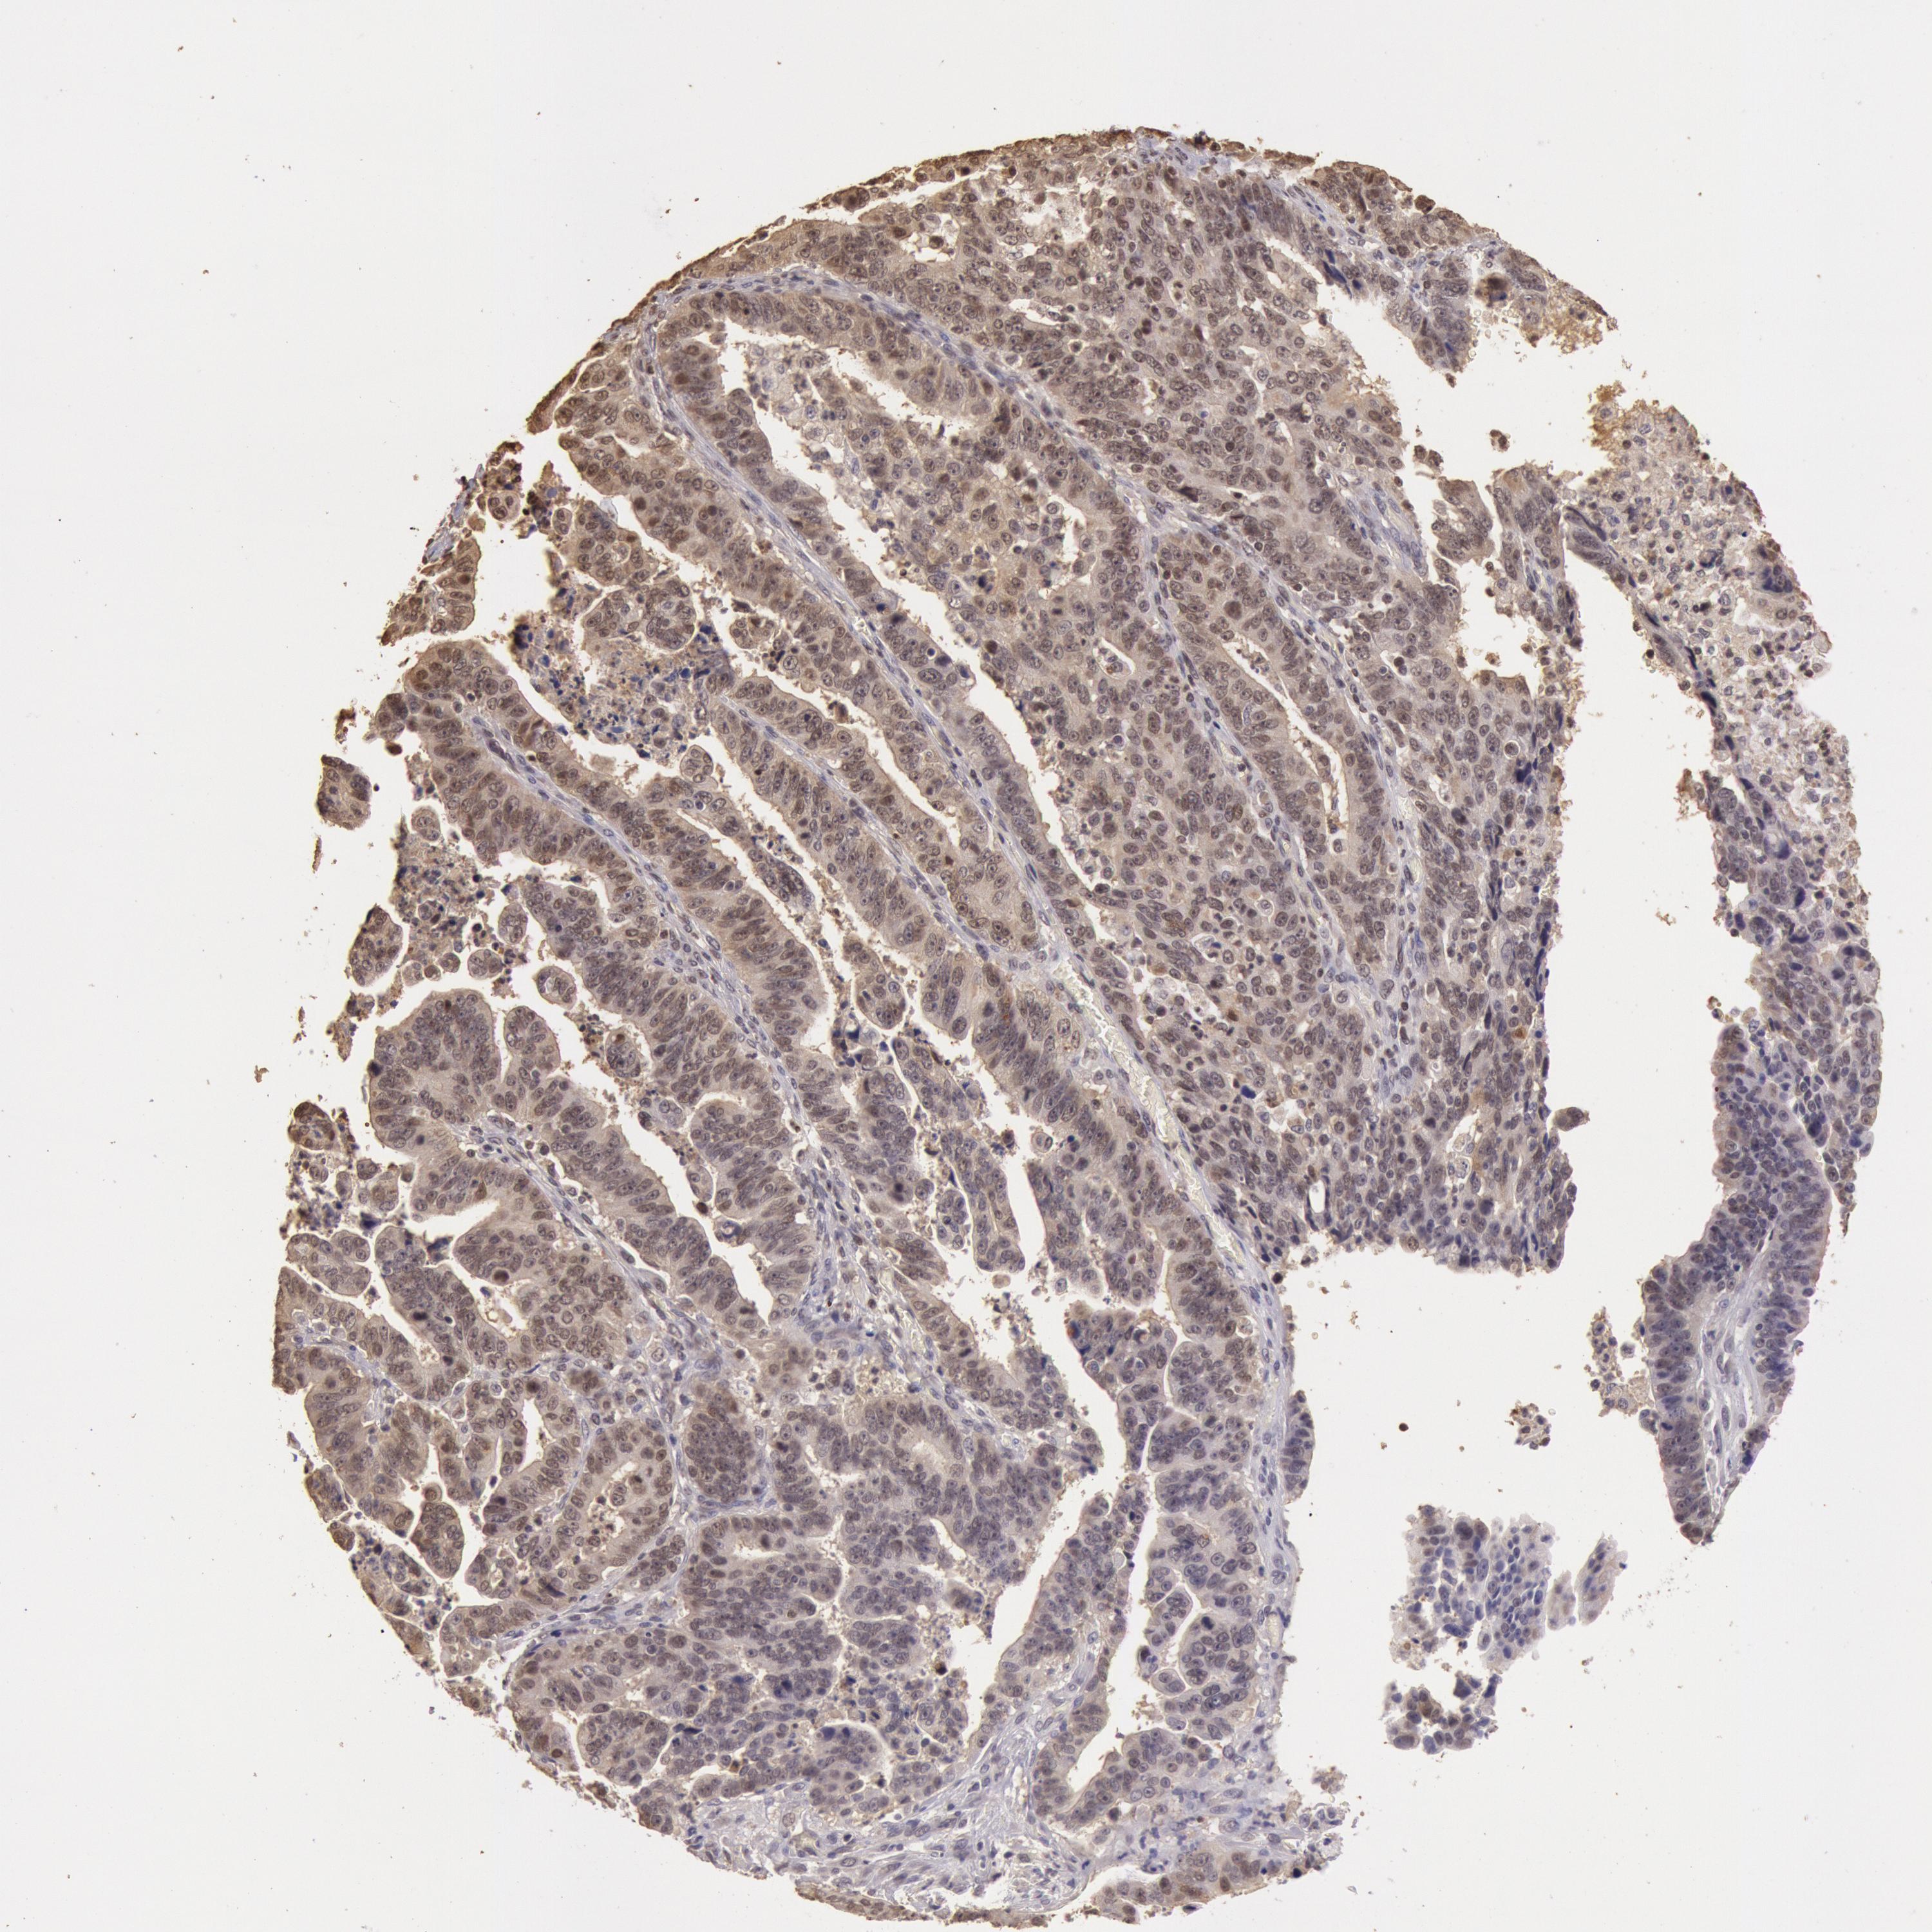

STOMACH CANCER - Protein expressioni

A mouse-over function shows sample information and annotation data. Click on an image to view it in a full screen mode. Samples can be filtered based on level of antibody staining by selecting one or several of the following categories: high, medium, low and not detected. The assay and annotation is described here.

Note that samples used for immunohistochemistry by the Human Protein Atlas do not correspond to samples in the TCGA dataset.

Antibody stainingi

Antibody staining in the annotated cell types in the current human tissue is reported as not detected, low, medium, or high, based on conventional immunohistochemistry profiling in selected tissues. This score is based on the combination of the staining intensity and fraction of stained cells.

Each image is clickable and will lead to virtual microscopy that enables deeper exploration of all samples and also displays staining intensity scores, fraction scores and subcellular localization as well as patient and tissue information for each sample.

Antibody HPA001401

Antibody CAB008670

Staining

High

Medium

Low

Not detected

Intensity

Strong

Moderate

Weak

Negative

Quantity

>75%

75%-25%

<25%

None

Location

Nuclear

Cytoplasmic/membranous

Cytoplasmic/membranous,nuclear

Adenocarcinoma, NOS